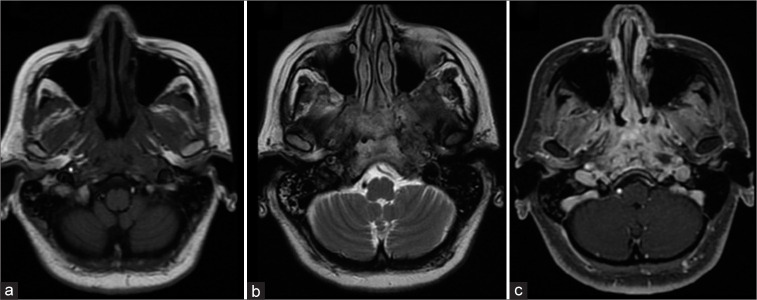

Magnetic resonance imaging (MRI) of the skull base at the level of the clivus and the petrous apex showed soft tissues as isointense to muscle tissue in T1-weighted sequence and hyperintense in T2-weighted as well as in fluid-attenuated inversion recovery sequence, with gadolinium enhancement in fat-saturated contrast-enhanced T1-weighted (T1+C+FAT) sequence, [Figure 2]. Loss of fat planes among soft tissue was identified with restriction in diffusion sequence, corroborated in apparent diffusion coefficient (ADC) sequence map, [Figure 3].

Figure 2:

Axial magnetic resonance imaging demonstrating a hypointense lesion with sphenoid boy and clival bone involvement (a) infiltrating nasopharyngeal submucous tissue (b) with a hypointense appearance in T1 and T2 sequences. Gadolinium enhancement in T1 of sphenoid and clival bone tissue.